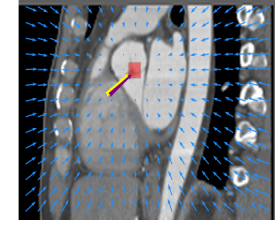

Finally, the proposed network was evaluated for the detection of five additional landmarks: the left coronary ostium, the bifurcation of the LM into the LAD and the LCx, and the origin of the left, non-coronary, and right aortic valve commissures (see Fig. 2). Fig 3 shows vector fields visualizing the predicted displacement vectors in three viewing planes in an image from the test set (for more results, see Appendix). Table 3 lists the Euclidean distance errors between the predicted landmark locations and the reference landmark locations. In addition, box-and-whiskers plots are shown in Fig 4. The best results were obtained for the origin of the right aortic valve commissure. Detection of the origin of the left aortic valve had the most narrow distribution. Outliers were seen during detection of the right ostium, the bifurcation of the LM, and the origin of the non-coronary, and the left aortic valve commissure.

Refer to caption Refer to caption Refer to caption

Figure 3: Vector fields visualizing the predicted displacement vectors in the axial, coronal, and sagittal plane in an image from the test set where detection of the right coronary ostium was performed. The magnitudes of the vectors should point at the right ostium, but they are rescaled for visualization purposes. The red squares indicate posterior probabilities larger than 0.5, obtained by the classification network for image patches. Reference and computed landmark annotations are indicated with a yellow and purple arrow, respectively.